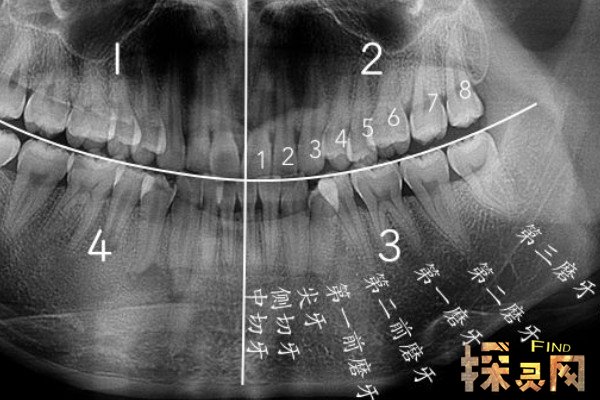

智齿是人类口腔内牙槽骨上最里面的第三颗磨牙,由于它经常会产生疼痛感,很多人选择将其拔掉,但部分人表示拔智齿后悔死了,那么这是为什么呢?快和小编去看看吧。

人在成年之后一般都会长智齿,在其生长期间可能会出现牙龈肿痛的情况,严重影响人们的日常生活,所以很多医生都建议将其拔掉,但总有人会因为拔掉后出现的不良反应而后悔。事实上,智齿对人的危害没有那么大,如果其生长状态比较良好,则没有强行拔除的必要,除非是畸形智齿。

拔智齿会产生一定的后遗症,当这颗牙齿被拔掉之后,牙齿间的缝隙会变大,由此就会导致食物残留在缝隙中,形成牙石后会直接引起牙龈问题。此外,智齿拔掉后,该位置的牙槽骨也会被吸收掉,让前面的牙齿变得松动,然后引发牙周炎,如果不及时治疗,就会诱发不良并发症。